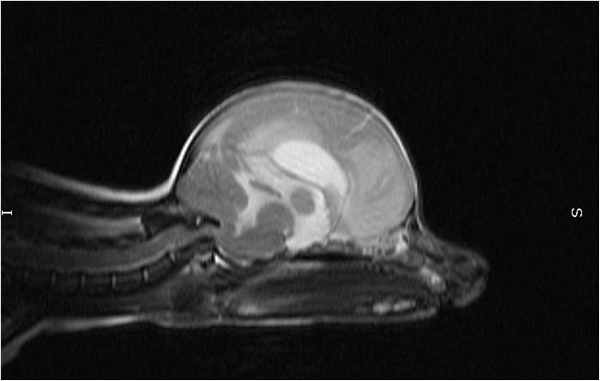

МРТ краниовертебрального сочленения в сагиттальной плоскости (А) и художественное исполнение (Б).

Показаны покровная мембрана (стрелка) и поперечная связка атланта (толстая стрелка).

БА — базион; ОП — опистион; ПМем — передняя атланто-затылочная мембрана; ЗМем — задняя атланто-затылочная мембрана;

З—Зуб; Ост2 — остистый отросток С2;ПД — передняя дуга атланта (тонкая стрелка); ЗД — задняя дуга атланта. Крестообразная, поперечная, крыловидные и добавочные связки.

А. МРТ во фронтальной плоскости. Б. рисунок.